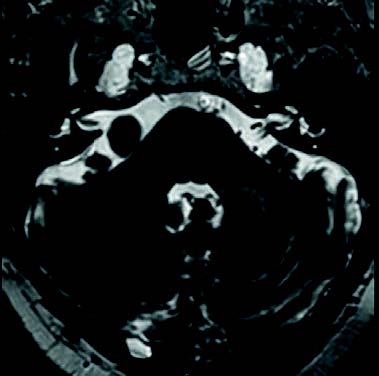

Mujer de 76 años con un traumatismo craneal y pérdida de conciencia. Cuatro meses antes le detectaron en un TAC craneal una formación calcificada en ángulo pontocerebeloso.

Mujer de 76 años con un traumatismo craneal y pérdida de conciencia. Cuatro meses antes le detectaron en un TAC craneal una formación calcificada en ángulo pontocerebeloso. Tiene antecedentes de vértigos posicionales desde hace años por problemas de columna. Fue operada de una tumoración lipomatosa grande en la espalda hace 2 años y desde entonces tiene una contractura. Refiere pérdida de audición antigua, más intensa por oído derecho, y ahora también tiene pérdida de olfato.

En la exploración, los tímpanos son normales y la audiometría presenta una hipoacusia sensorial bilateral de 50 dB de media en OD y de 45 dB en OI, con caída en agudos. Se pide RMN craneal.